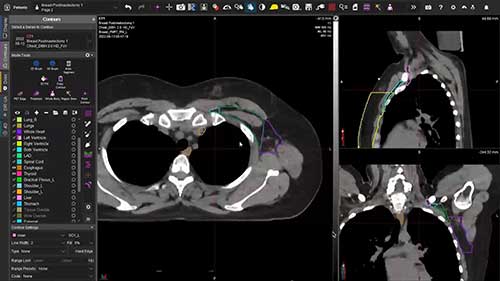

美国斯克里普斯质子治疗中心

类别:放射治疗技术

简介:斯克里普斯质子治疗中心位于加州的圣地亚哥市,是全美15家质子治疗中心之一,也是目前技术最先进的质子治疗中心。

放射治疗技术

质子治疗